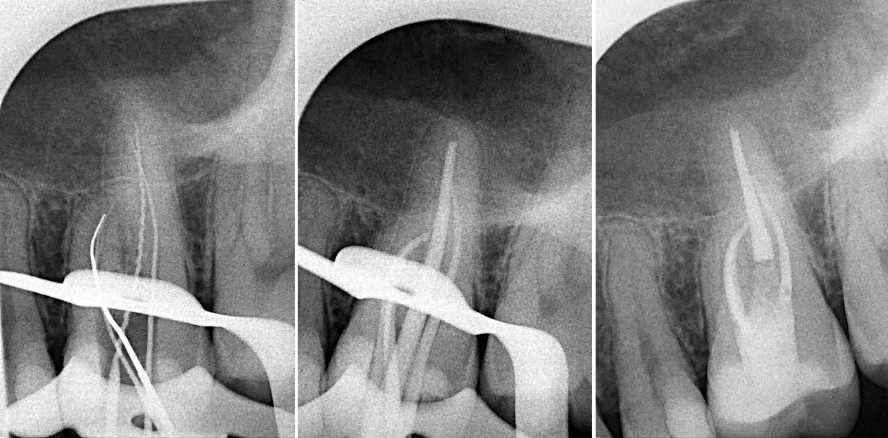

Im ersten Fall geht es um einen männlichen Patienten im Alter von 85 Jahren. Der behandelnde Zahnarzt stellte einen Abszess an Zahn 42 fest und trepanierte den Zahn. Das Auffinden der Wurzelkanäle erwies sich als schwierig, da die Wurzelkanäle stark obliteriert waren. Der Kollege überwies den Patienten in unsere Praxis. Ein chirurgischer Eingriff aufgrund des Abszesses war nicht erforderlich, dieser wurde bereits behandelt, der Abheilungsprozess mit systemischer Antibiose unterstützt. Dieser Fall ist ein Musterbeispiel für die Anwendung der TruNatomy™-Feilen: Es wurden zwei Wurzelkanaleingänge gefunden, die sich dann zu einem Kanal verbanden. Wir haben klassisch aufbereitet, mit Komposit verschlossen und an den Hauszahnarzt zur weiteren Behandlung zurücküberwiesen (Abb. 1–3).